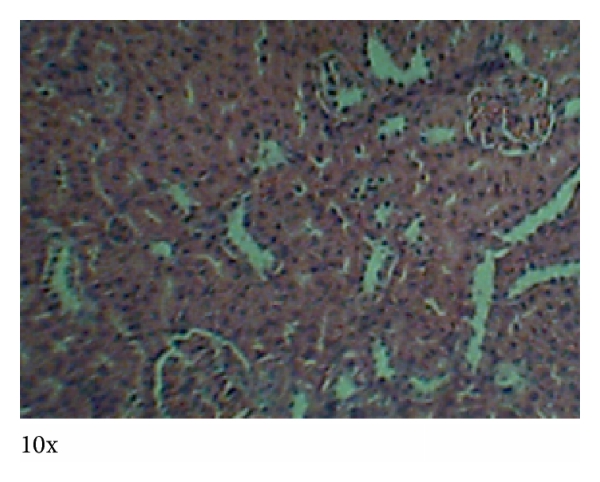

3.4. Histopathology

Photomicrographs of tissues prepared from control and animals treated with MOE at different dose levels are presented in Figures 5–8. No observable cardiomyopathy was noted in the heart (Figure 5). Figure 6 showed no observable ulceration. The epithelial cells of the stomach are intact. Figure 7 also showed no observable histological lesions in the glomerulus and the tubules. There were no observable histological lesions in the sinusoids and central vein of the liver (Figure 8).

The kidneys are concerned with the elimination of drugs from the body and are likely to be affected during such toxicity studies at high doses. In the treated male rats, creatinine levels were reduced compared to the controls () while urea levels were inconsistent among the groups. This suggests that MOE did not adversely affect the integrity of the renal system [29]. Also, histopathological examinations did not reveal any observable histological lesions in the glomeruli and the tubules (Figure 7). However, the reduction in creatinine levels may be deemed to be positive effect of MOE on the renal system, which could be exploited therapeutically. These findings are consistent with those reported by Isitua and Ibeh, 2013 [17].